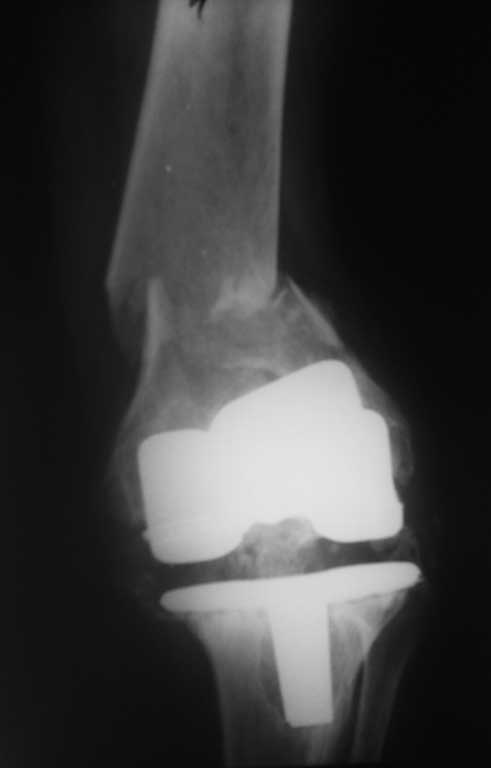

Перипротезный перелом бедра.

Пациентка 54 г. Два года назад выполнено протезироввние коленного сустава в одном из федеральных учереждений.

Обратилась на консультацию в связи с выраженым болевым синдромом. В тот момент находилась на лечении в терапевтичесом отделении по поводу язвенной болезни желудка. При осмотре клинико-Рлогическая картина нестабильности компонентов протеза. рекомендовано оформление инвалидности и реэндопротезирование по квотам. Через неделю пациетна упала. в результате падения переипротезный перелом на фоне нестабильного протеза. Переведена в травм.отд. наложено скелетное вытяжение. Какие варианты лечения возможны? Финансово несостоятельна.

Его (при грамотном применении) никто не отменял и на ревизию здесь ничто не повлияет. Тем более судя по снимкам имеется нестабильность тибиального компонента а про бедренный компонент не убедительно. Пока больна дождется квоты (учитывая нашу действительность) глядишь и перелом бедра срастется не вытяжении.